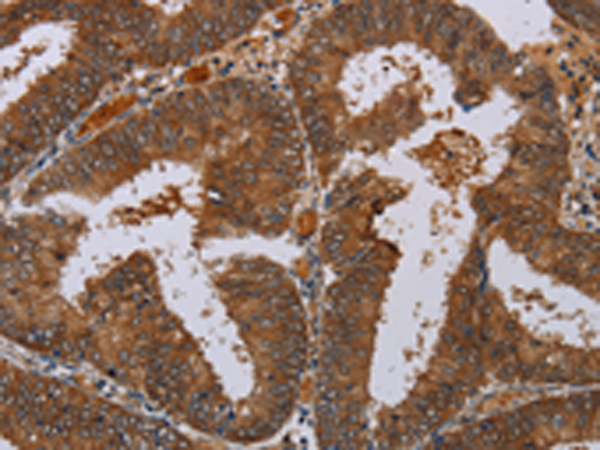

分类: 科研抗体货号: P01553别名: ATLD; HNGS1; MRE11A; MRE11B应用: WB,IHC反应种属: Human, Mouse, Rat